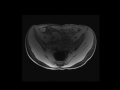

Crohn's ileitis

MR enterography demonstrates thickening and hyperenhancement of the distal ileum in a patient with active Crohns related ileitis.